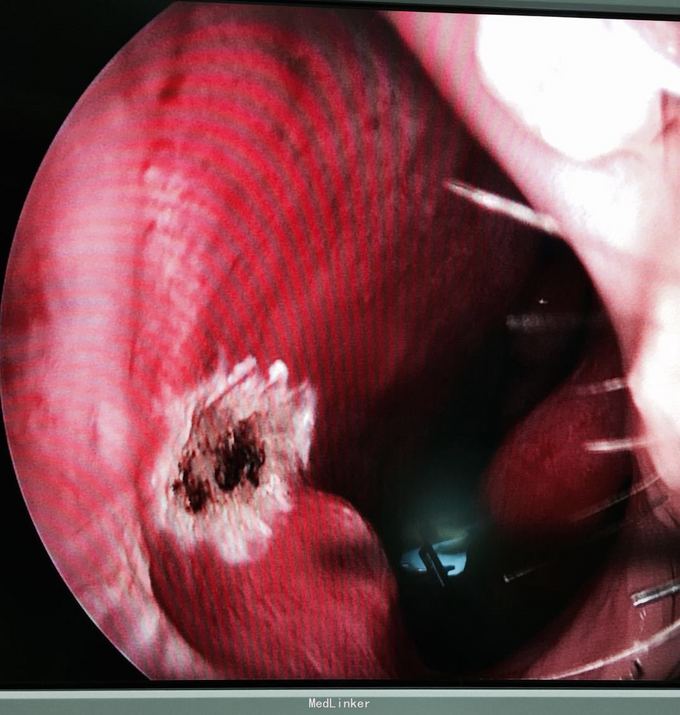

诊断:鼻中隔新生物(血管瘤可能) 处理:局部麻醉鼻内镜下行新生物摘除,双极电凝止血。 术后病理:肉芽性血管瘤

随访已2周,未再出血,局部愈合好。 讨论: 1,鼻出血是耳鼻咽喉科常见病症,little 's 区多发 2,肉芽性血管瘤常炎症或外伤(如喜挖鼻者)后,本病例起于感冒后,炎症是一个病因。 3,鼻出血需根据病因予以相应治疗。